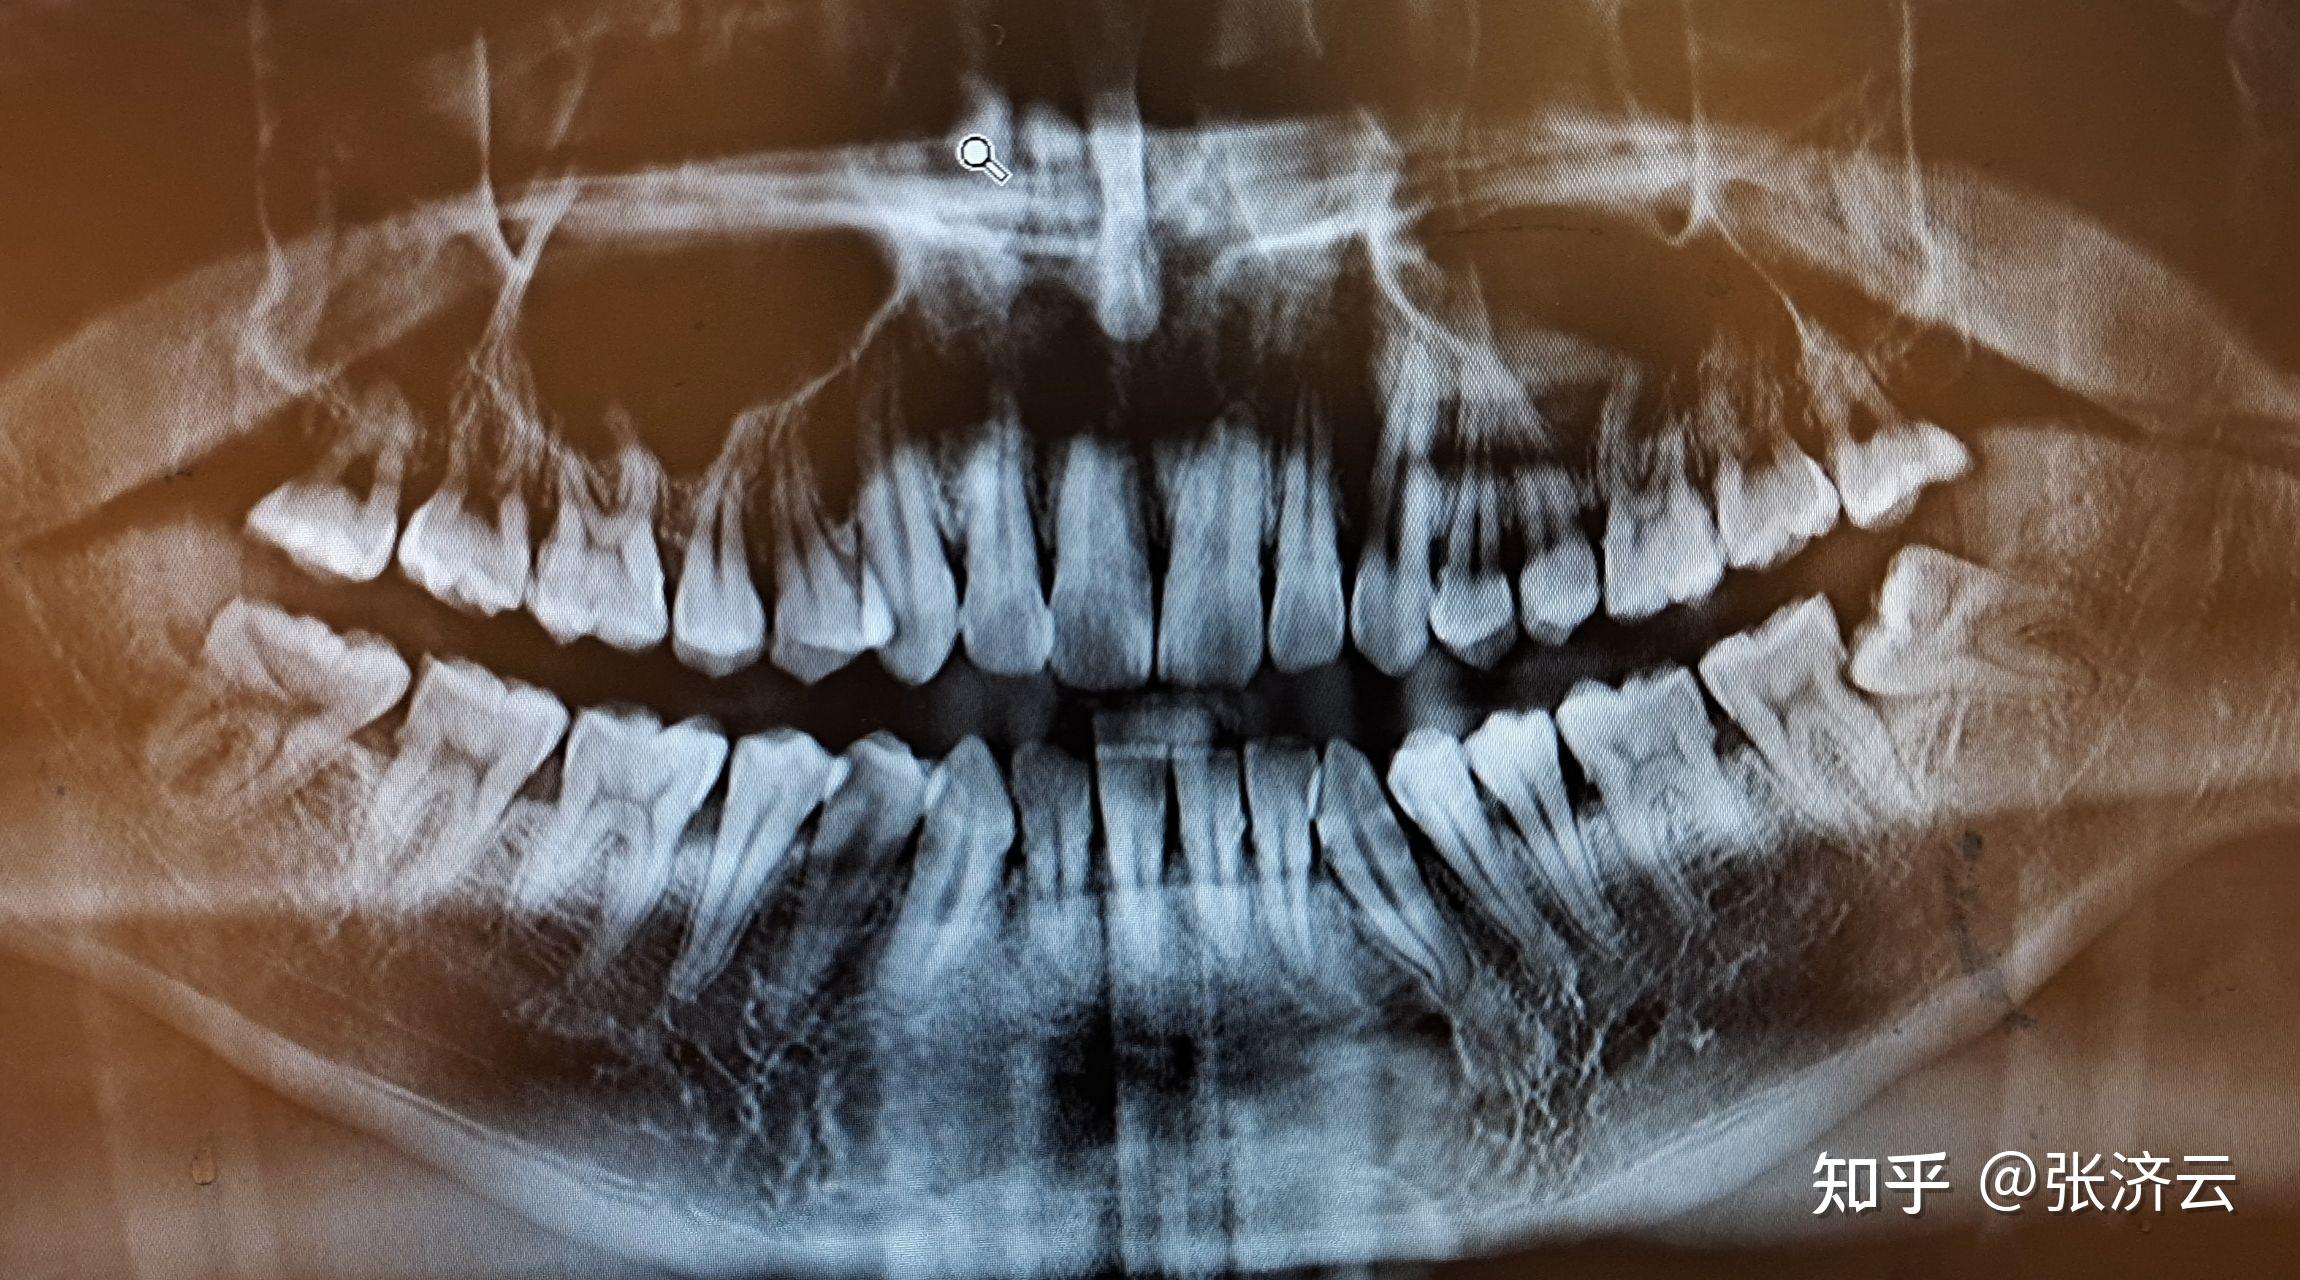

牙周炎龈下刮治前后

做47远中牙周袋的龈下刮治术.

图13.做47远中牙周袋的龈下刮治术.